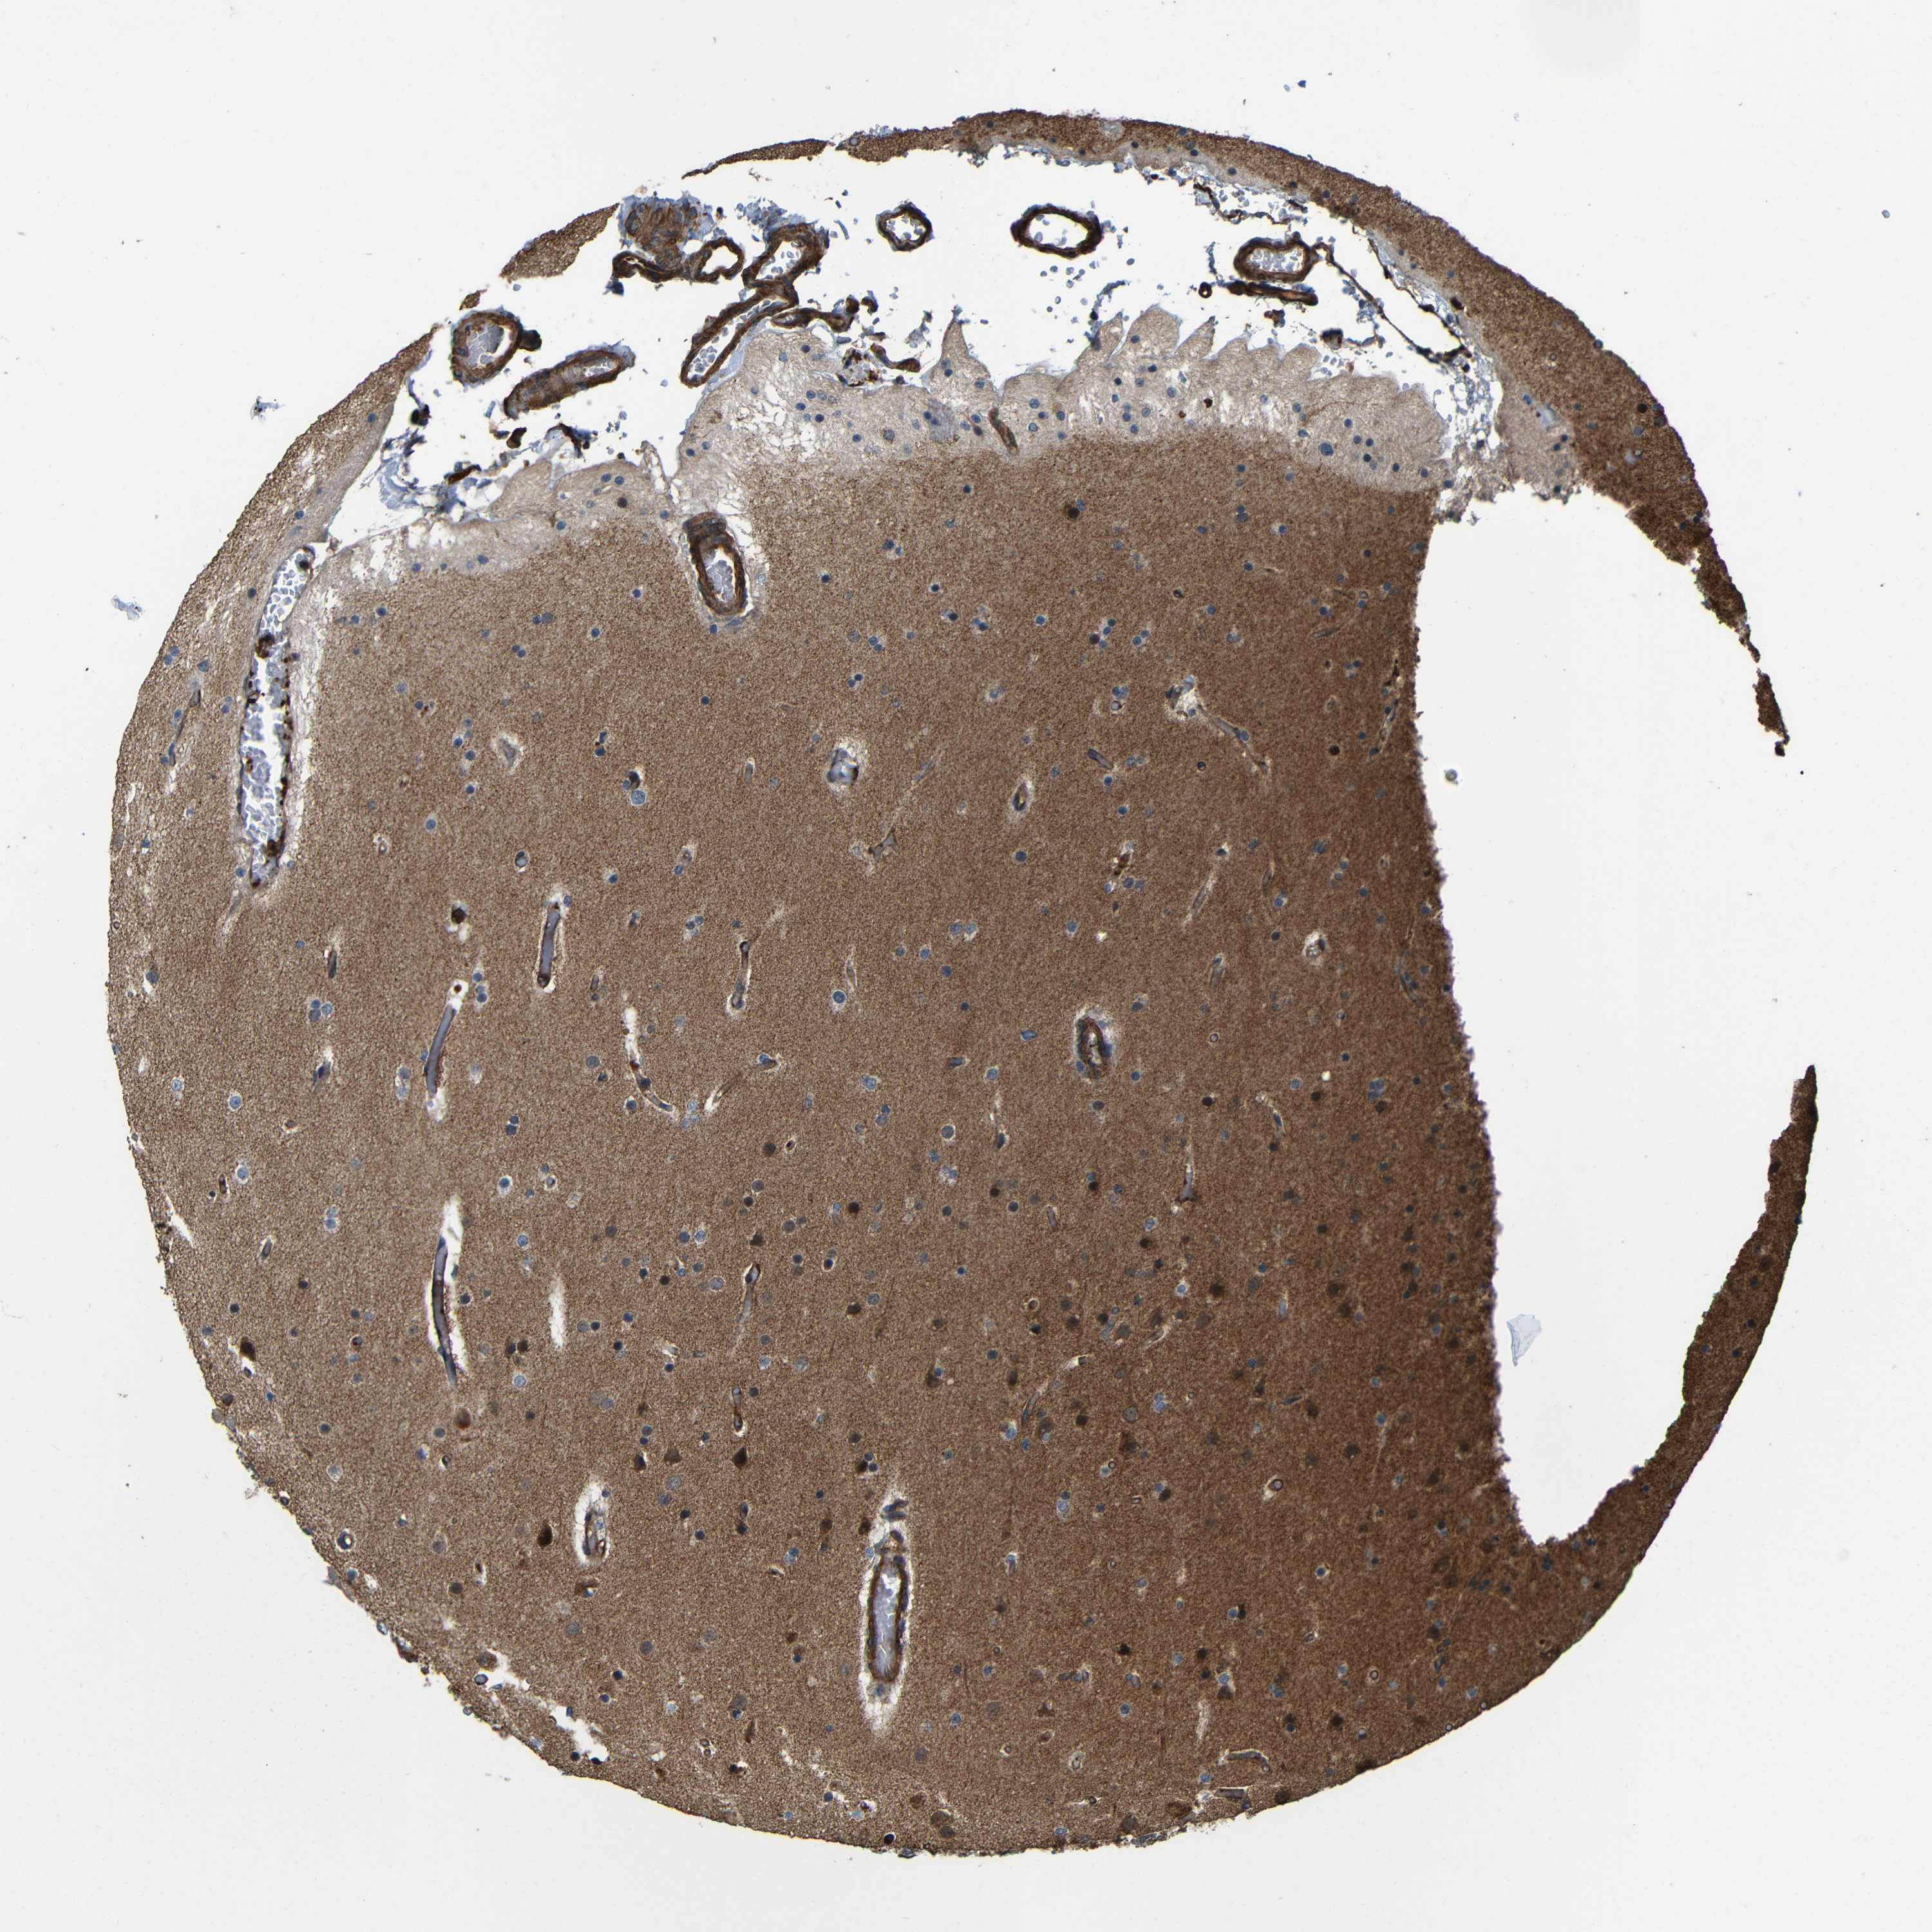

GLIOMA - Protein expressioni

A mouse-over function shows sample information and annotation data. Click on an image to view it in a full screen mode. Samples can be filtered based on level of antibody staining by selecting one or several of the following categories: high, medium, low and not detected. The assay and annotation is described here.

Note that samples used for immunohistochemistry by the Human Protein Atlas do not correspond to samples in the TCGA dataset.

Antibody stainingi

Antibody staining in the annotated cell types in the current human tissue is reported as not detected, low, medium, or high, based on conventional immunohistochemistry profiling in selected tissues. This score is based on the combination of the staining intensity and fraction of stained cells.

Each image is clickable and will lead to virtual microscopy that enables deeper exploration of all samples and also displays staining intensity scores, fraction scores and subcellular localization as well as patient and tissue information for each sample.

Antibody CAB013717

Staining

High

Medium

Low

Not detected

Intensity

Strong

Moderate

Weak

Negative

Quantity

>75%

75%-25%

<25%

None

Location

Nuclear

Cytoplasmic/membranous

Cytoplasmic/membranous,nuclear

Glioma, malignant, High grade

Glioma, malignant, Low grade